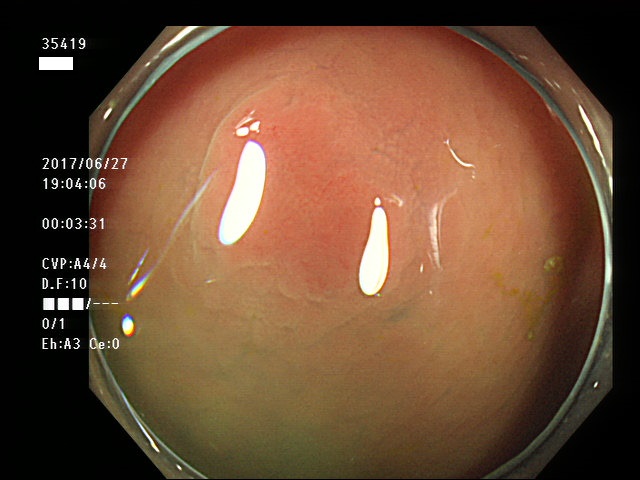

上記100名より抽出した平坦・陥凹型腺腫・SSAP(=癌化の危険が高いが見落としやすい病変)の内視鏡写真

35403 35404 35405 35409 35410 35412 35413 35414 35416 35417 35418 35419 35420 35421 35426 35429 35430 35433 35434 35435 35438 35439 35440 35444 35445 35447 35449 35450 35451 35452 35453 35454 35458 35460 35463 35464 35466 35468 35469 35470 35472 35473 35478 35479 35481 35483 35485 35489 35490 35491 35492 35493 35498 ・・・・・の54名